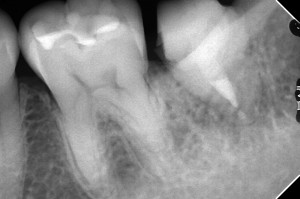

樋状根で苦労しやした

かなり自然廷出し、縁上マージンになっていることに注目。

動揺もなく、きれいになりました

4か月かかりました。

移殖後、スーパーボンドで固定してはいけない。これは自然提出を妨げる可能性ありますものね。

外科+根管治療のコンビネーション症例ですね。